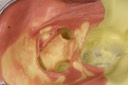

Alan Chinn #3 caries removal 2

Alan Chinn #3 prep